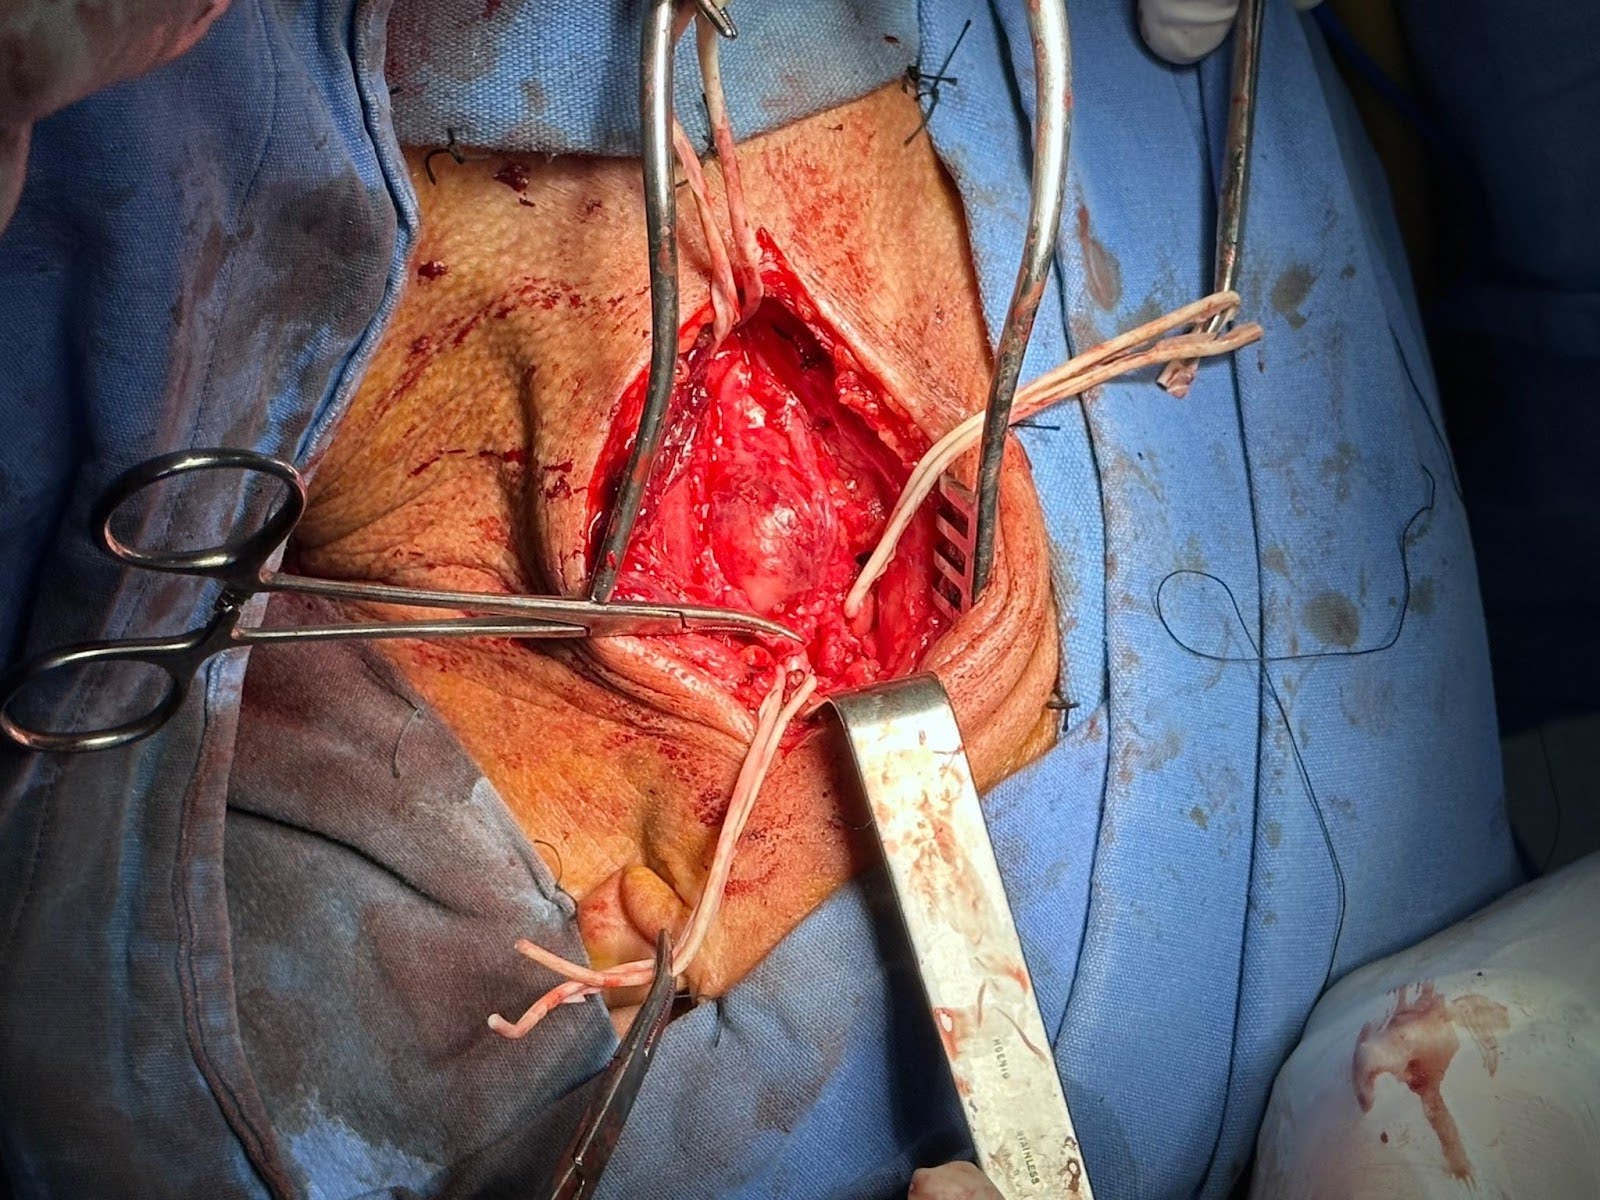

Während der Operation wurde das umgebende fibrotische Gewebe präpariert, und die Aneurysmawände wurden getrennt und freigelegt, bis sie identifiziert wurden.

Sobald das Aneurysma sowie die Struktur der Arteria carotis communis, der Arteria carotis interna und der Arteria carotis externa identifiziert sind, wird zuerst eine externe Carotisklemmung durchgeführt, um eine längere Zeit mit der Klemmung der inneren Halsschlagader zu vermeiden. Die Freilegung des Operationsfeldes ist in Abbildung 3 zu sehen.

Abbildung 3. Bild der chirurgischen Exposition. Referenz der Arteria carotis communis, der Arteria carotis externa und der Arteria carotis interna mit Aneurysma im proximalen Teil der Bifurkation.

Die Arteria carotis externa ist in ihrem distalen Teil ligiert, und der Anastomosenmund bleibt im proximalen Teil erhalten.

Anschließend wird die Arteria carotis communis und die Arteria carotis interna von der unteren und oberen Grenze des Aneurysmas für die Aneurysmorrhaphie geklemmt und der proximale Ursprung der Carrotis interna ligiert. Die Anastomose wurde mit einer doppelarmigen, nicht resorbierbaren monofilen Gefäßnaht unter Verwendung der Fallschirmtechnik an der proximalen Arteria carotis externa und der distalen Arteria carotis interna durchgeführt, wobei ein Aneurysmaausschluss und eine externe Carotistransposition erzielt wurden.